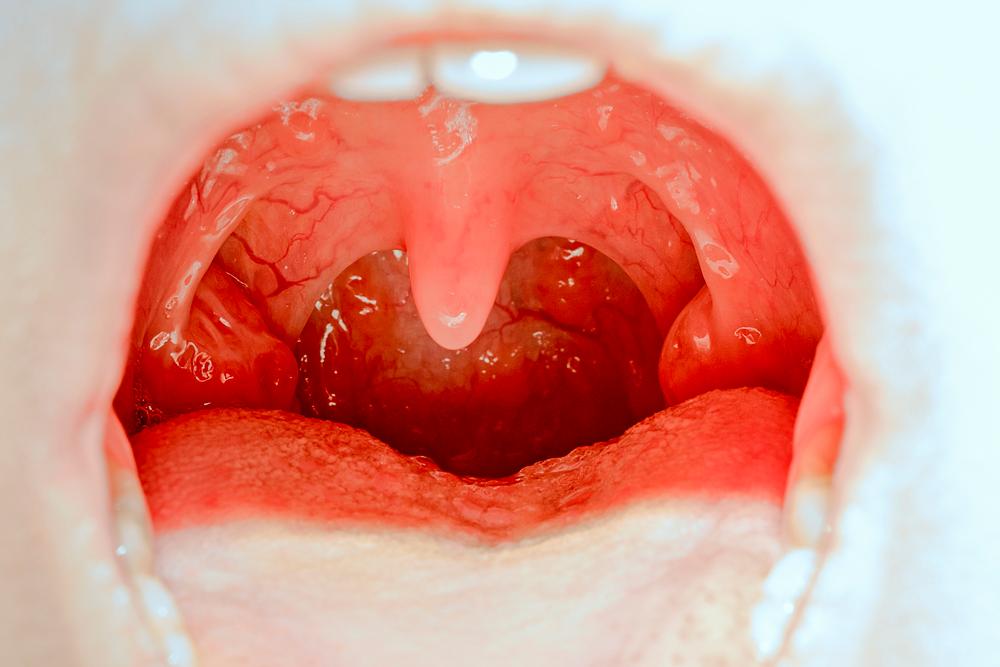

La irritación de las mucosas resulta en la emisión de histamina, un compuesto involucrado en las respuestas nerviosas locales del sistema inmunitario que va a hacer exactamente eso, activar las células nerviosas de tu nariz para que envíen una señal al cerebro que diga: ¡Debemos estornudar! Así, a través del nervio trigémino (encargado de las sensaciones de la cara y alguna de sus funciones motrices), el paladar blando y la úvula se deprimen al mismo tiempo en que la parte trasera de la lengua se elevaba a fin de tapar parcialmente el pasaje por el que se escapa el aire de la boca para que salga principalmente por la nariz. Curioso, ¿no?